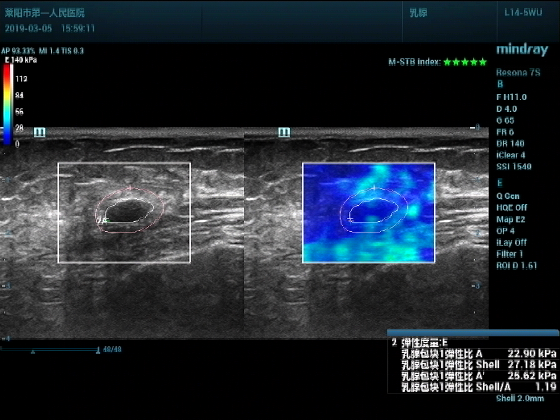

超声入门贴994--乳腺纤维瘤(弹性成像)